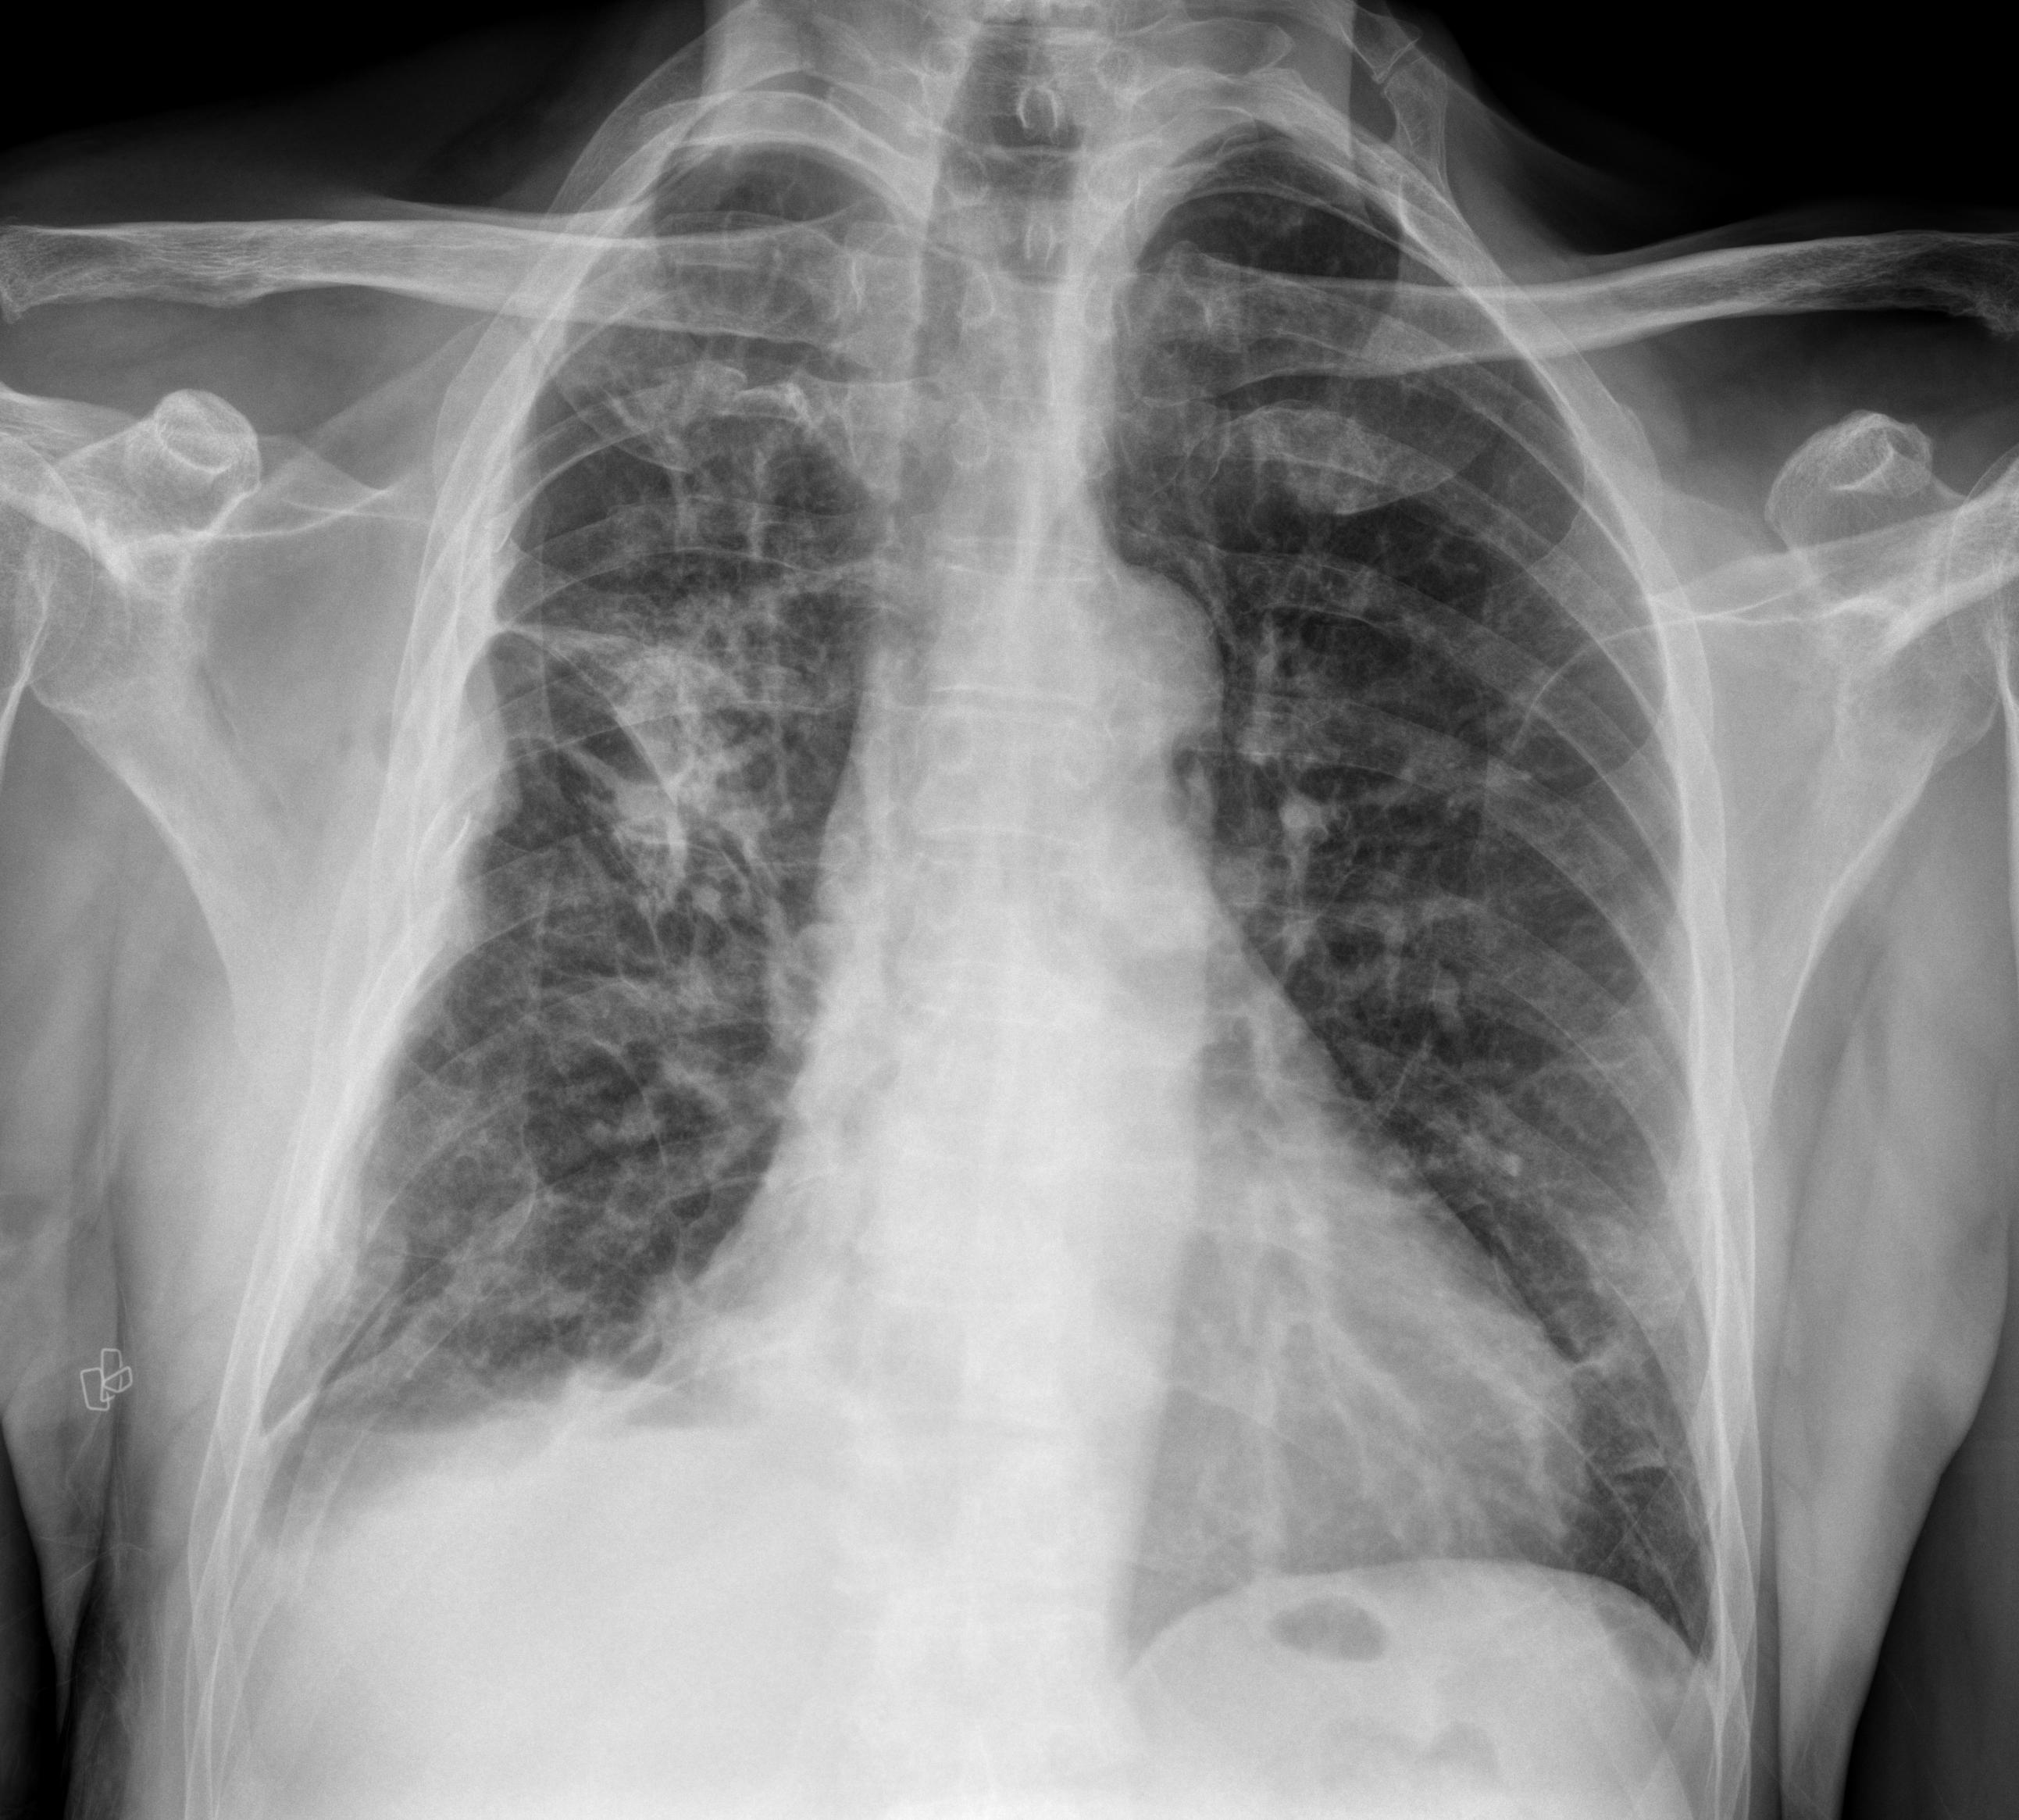

1 Tórax portátil